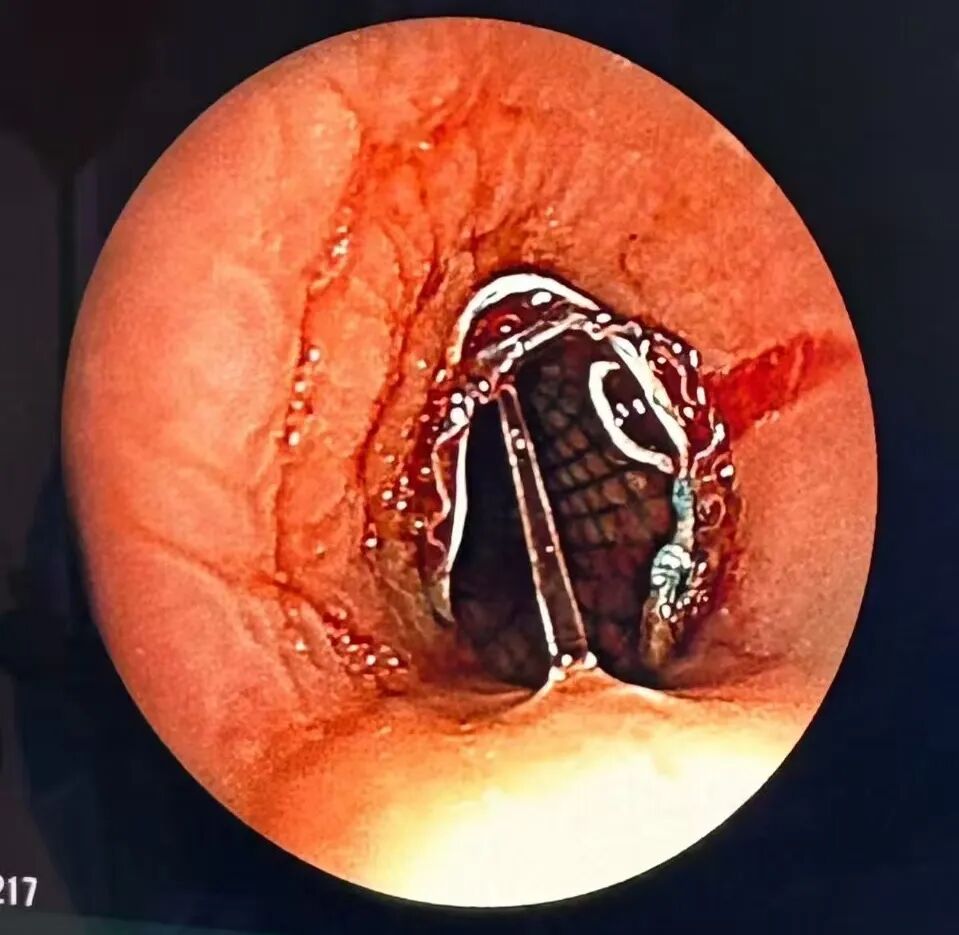

就在紧张的抢救治疗过程中,患者心率突然由144次/分下降至58次/分、指脉氧下降至67%,呼之不应。生命体征眼看就要维持不住。立即采取胸外按压、肾上腺素1mg静脉推注、床旁支气管镜引导下气管插管术等急救措施。仅用时4分钟,经鼻气管插管成功。患者自主心率恢复,指脉氧逐渐升高。这一场突如其来的危机终于安然度过。支气管镜下医生看到气管支架上方被大量坏死组织覆盖并且气管被坏死组织和血性黏痰几乎堵塞。随即给予钳夹坏死组织,并清理吸引管腔内的大量粘稠分泌物,同时适时调整了支架位置,经反复判断确认支架位置固定良好。

在接下来的治疗中,每日气管镜评估气管支架位置并密切观察患者的咳痰能力,且动态调整镇痛镇静肌松用药确保镇痛镇静深度。3日后复查支气管镜见气管支架位置稳定且无明显坏死组织和分泌物。患者对气道支架耐受良好,氧合指数稳定,遂拔除气管插管,序贯CPAP辅助通气。